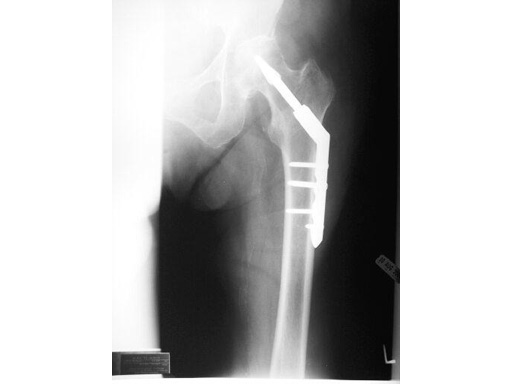

The LCP Dynamic Helical Hip System is a stainless steel plate and helical blade construct used to treat stable and unstable intertrochanteric and pertrochanteric fractures. The system can also be used to treat certain basilar neck and subtrochanteric fractures. A significant feature of the plate portion of the system is the incorporation of a barrel that contains a mechanism which allows the surgeon to lock rotation of the helical blade intraaoperatively. This separate key allows for the free rotation of the helical blade shaft within the barrel, giving surgeons the opportunity to position and fine tune the placement of the plate along the shaft of the proximal femur. When the desired plate position is achieved, the key can then be activated, lock rotation, and still allow for dynamic compression of the fracture. As the LCP DHHS system utilizes a helical blade, it is also a significant improvement over traditional hip screws. In mechanical testing, the helical blade has proven to resist rotational and cantilever loads far greater in fatigue and static testing than traditional hip screws. The helical blade requires less bone removal in the femoral head, therefore preserves as much bone around the construct as possible. The combination of the helical blade and the new LCP side plate create a very stable secure construct which improves upon the original concept of the sliding dynamic hip screw implant. The plates feature locking compression holes which allow for the use of 5.0 mm locking head screws or 4.5 mm cortex screws. The plate design incorporates a limited contact profile and a tapered end for easier insertion through smaller incisions. The LCP DHHS is available in a 130 version with 4.5 and 6 holes, as well as a 135, 140, and 145 with 26 holes each.